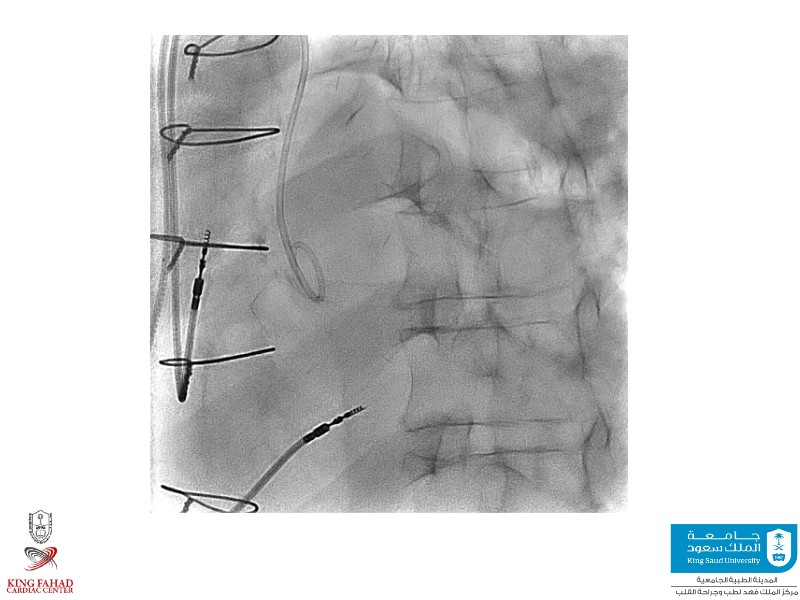

This session helps you anticipate and address complex scenarios such as mitral valve-in-valve, TAV-in-SAV, and valve-in-valve-in-valve procedures. Learn from expert case discussions that explore procedural strategies, technical challenges, and best practices to optimize outcomes in redo structural heart interventions.

- To anticipate and manage second valve scenarios with SAPIEN 3 Ultra RESILIA, including mitral valve-in-valve, TAV-in-SAV, and TAV-in-TAV

- To understand procedural strategies and challenges in complex redo scenarios using SAPIEN 3 Ultra RESILIA